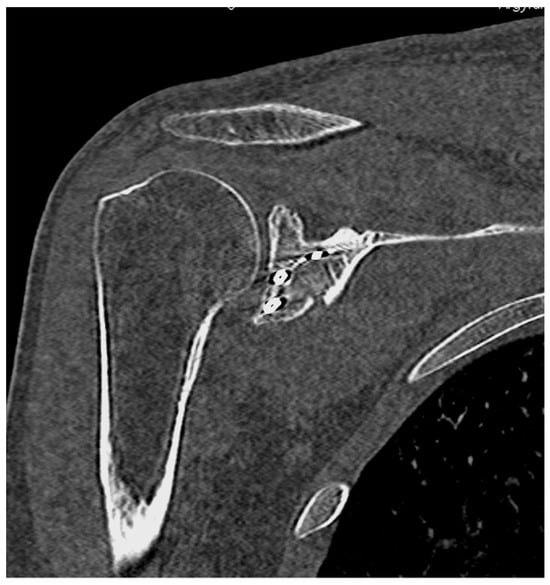

6.1. Ideberg Type III Fractures

- Tao, M.A.; Garrigues, G.E. Arthroscopic-Assisted Fixation of Ideberg Type III Glenoid Fractures. Arthrosc. Tech. 2015, 4, e119–e125. [Google Scholar] [CrossRef] [PubMed]

- Acharya, P.; Arora, B.; Pinto, N. Arthroscopy Assisted Percutaneous Fixation of Ideberg Type Iii Glenoid Fractures. J. Orthop. Case Rep. 2015, 5, 41–43. [Google Scholar] [CrossRef]

- Yang, H.B.; Wang, D.; He, X.J. Arthroscopic-assisted reduction and percutaneous cannulated screw fixation for Ideberg type III glenoid fractures: A minimum 2-year follow-up of 18 cases. Am. J. Sports Med. 2011, 39, 1923–1928. [Google Scholar] [CrossRef] [PubMed]

- Bonczek, S.J.; Hutchinson, R.; Chakravarthy, J. An innovative method of fracture reduction in an arthroscopically assisted cannulated screw fixation of an Ideberg type III glenoid fracture. Int. J. Shoulder Surg. 2015, 9, 56–59. [Google Scholar] [CrossRef]